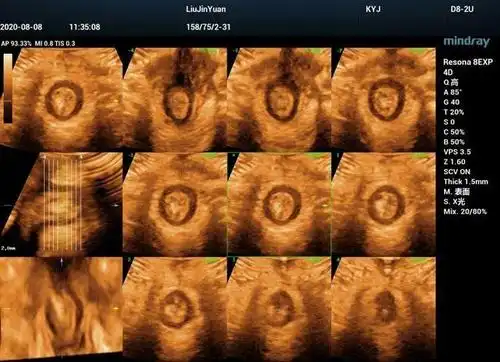

直肠及肛管超声诊断

肛周炎性疾病超声诊断

高手进阶胎儿肛门超声检查及肛门闭锁